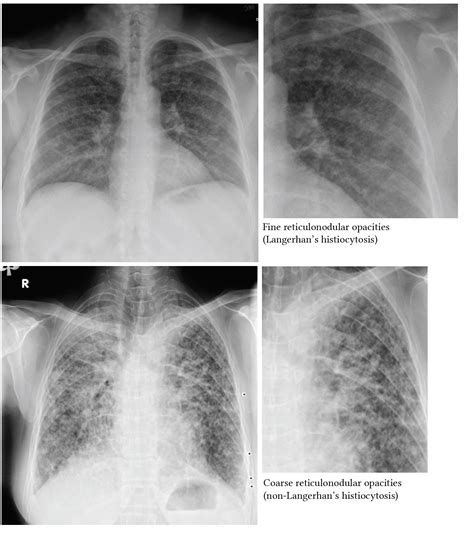

Types of Lung Opacities

Lung opacities can be categorized into several types based on their appearance and characteristics:

• Ground-glass opacity: This refers to an area of increased lung density that does not obscure the underlying bronchial structures. It can be caused by conditions such as interstitial lung disease or early stages of pneumonia.

• Inflammation: Conditions such as interstitial lung disease, sarcoidosis, and hypersensitivity pneumonitis can cause inflammation and subsequent lung opacities.